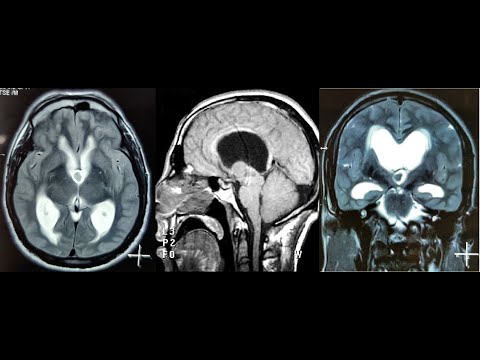

Hellow guys, Welcome to my website, and you are watching COLLOID CYST 3RD VENTRICLE NAVIGATION GUIDED MICROSURGERY -dr suresh dugani/HUBLI/INDIA. and this vIdeo is uploaded by drsuresh dugani NEUROSURGERY EDUCATIVE VIDEOS ATLAS at 2017-07-11T09:30:43-07:00. We are pramote this video only for entertainment and educational perpose only. So, I hop you like our website.